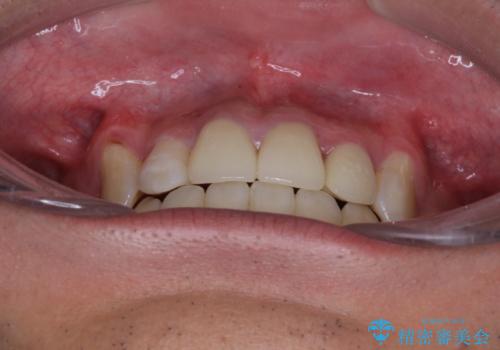

デコボコと変色した前歯 抜歯矯正と審美歯科治療

前歯の歯列が整ったことで、歯磨きが大変やりやすくなり、患者様には大変満足していただけました。